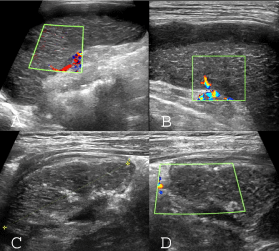

Figure 3: Sonographic pattern of splenic infarction in CGD case: A,B) Normal size spleen with peripheral and subscapular hypoechoic area; the splenic parenchyma has an interspersed hyperechoic linear striation and no vascular blood flow detected in splenic parenchyma. C,D) Follow up ultrasound images; decrease of spleen size and shrinkage border with capsular and parenchymal calcification without significant revascularization. View Figure 3

In second visit on 3.5 month next, the child was well being and without any abdominal discomfort. The follow up ultrasound shows spleen size to decrease (42 mm) with shrinkage border, capsular and paranchymal calcification, and without significant revascularization (Figure 3C and Figure 3D).